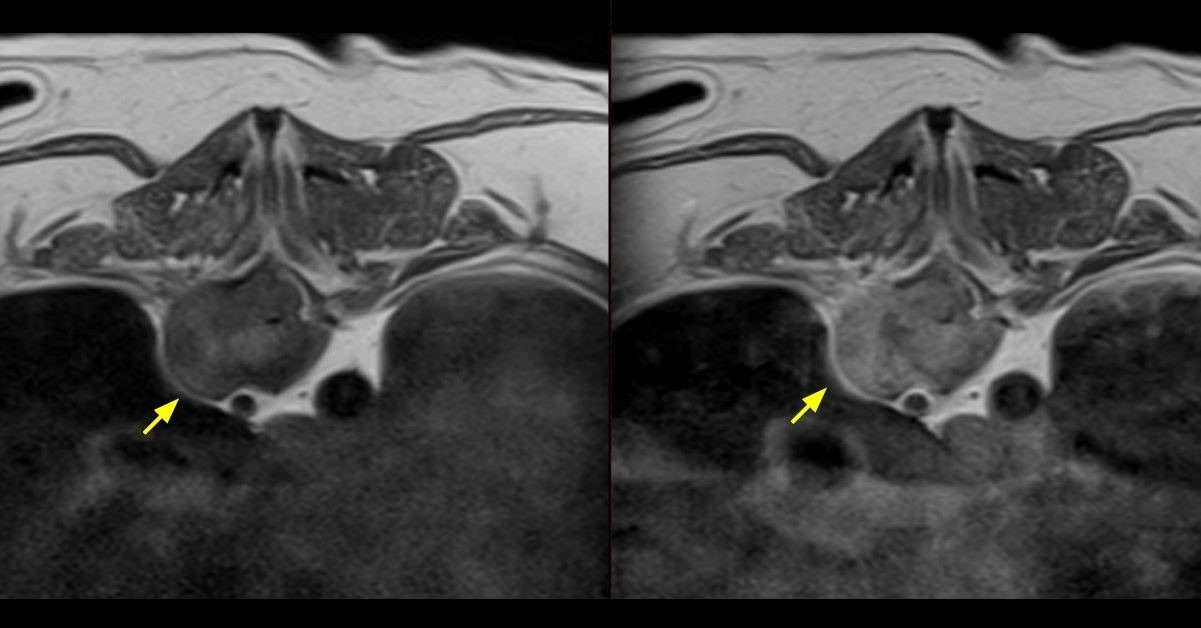

탁구의 척추 MRI 사진. T10 추체에서 종괴가 발견됐으며 골융해가 일어났다.

탁구의 10번 흉추에서 자라나는 종괴의 모습.

전화를 끊었다. 수의사가 카톡으로 파일을 보냈다. 여러장의 MRI·CT 촬영 사진과 함께 수의사의 소견이 적혀 있었다. 실체를 알 수 없었던 고통의 증거가 명백히 드러났다.

악성 종양은 탁구의 몸을 광산 삼아 척추·신장·어깨뼈 등 구석구석 돋아나고 있었다. 수의사만 이해할 수 있는 전문적인 단어로 가득한 정밀 소견이었지만 가슴을 후벼 파기에 충분했다.

‘흉추 10번 영역의 추체 주위의 종괴에 의한 척수의 심한 압박’